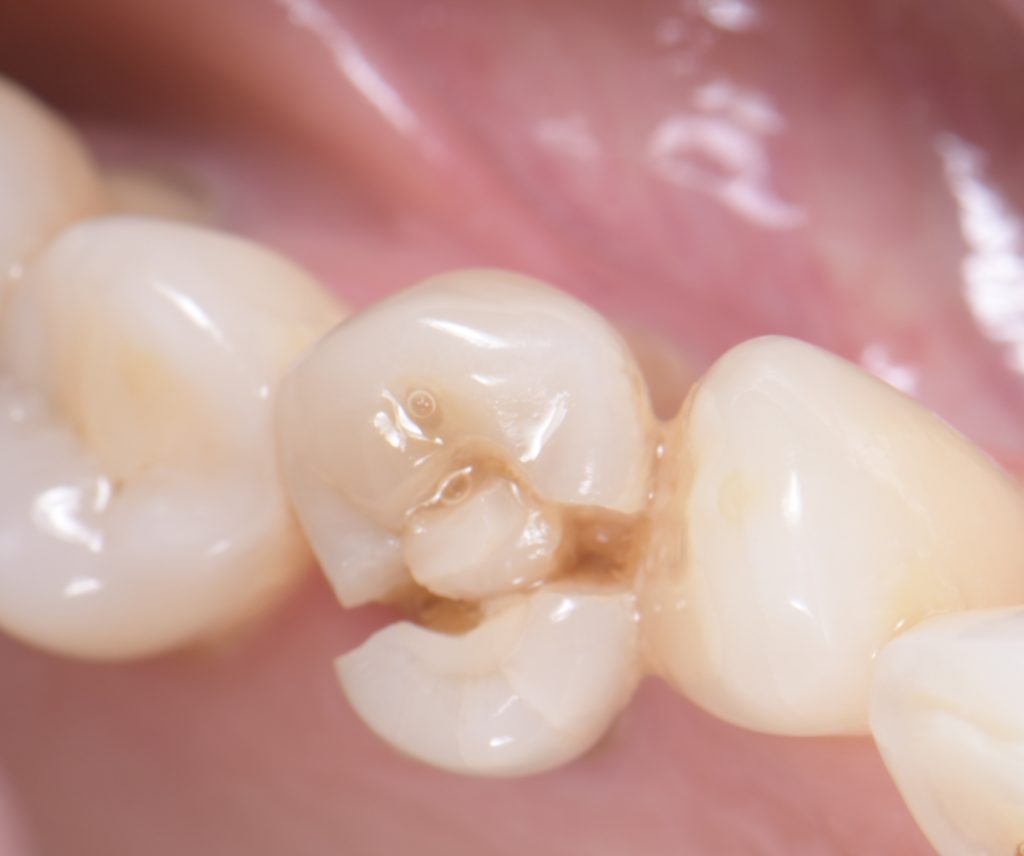

Fatigue is the breaking or fracturing of a material caused by repeated cyclic loads below the yield limit. Intraoral occlusal forces create this dynamic repetitive loading; thus, instead of a monotonic static load to fracture, normally patients experience a physiologic fatigue load. (Figs. 1-2)

Fatigue life is defined by the number of load cycles required for a specimen to fail for a given applied load. This number relies on several variables, such as stress level, stress state, cyclic wave form, fatigue environment and metallurgical condition of the material. However, fatigue life may also refer to a preliminary failure condition as opposed to complete fracture of the specimen.

The same is found with a fracture of a cusp or fragment of a tooth that has an intra-coronal restoration, such as an inlay, an amalgam, or a composite resin. (Figs. 5-6)

Fatigue cracks initiate and propagate in regions where the strain is most severe. This area of high deformation initiates a fatigue crack, which propagates under the applied stress through the material until the complete fracture, which once again may very well be evidenced for the first time while chewing sticky or soft food.